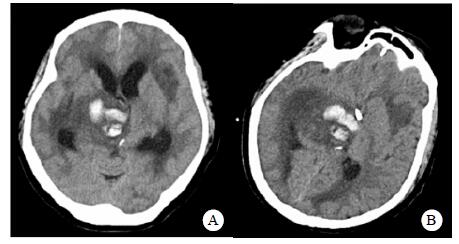

| A:右侧丘脑、左侧岛叶病变,伴脑室扩张;B:双侧脑室钻孔引流术后改变,脑室扩张较前(2019-09-29)好转,右侧丘脑、左侧岛叶病变伴出血 图 2 患者2019-09-29头颅CT平扫(A)和2019-09-30头颅CT平扫(B) |

转入ICU后呼吸机辅助通气、甘露醇100 mL/8 h静滴脱水、头孢呋辛1.5 g/12 h静滴抗感染,肠内营养等支持治疗。当晚血常规:白细胞13.3×109/L,中性粒细胞百分比85.3%,C反应蛋白17.1 mg/L,降钙素原0.64 ng/mL。脑室外引流术后次日血化验:白细胞16.6×109/L,中性粒细胞百分比92.8%,C反应蛋白78.4 mg/L;从脑室外引流管留取脑脊液检验:有核细胞6×106/L,红细胞1 960×106/L,蛋白含量1.717 g/L,葡萄糖4.72 mmol/L,细菌培养阴性,涂片未找到细菌;复查头颅CT示:脑室扩张好转,右侧丘脑、左侧岛叶病变伴出血(图 2);胸部CT示,两肺间质性肺炎下叶为著,较前(2019年6月21日)部分好转(图 3)。考虑到炎症指标升高,遂改哌拉西林他唑巴坦3.375 g/12 h静滴抗感染。此后经脑室外引流管反复留取脑脊液送检涂片及培养均阴性。术后第5天行“导航下立体定向颅内病灶活检术+双侧omaya囊置入术”,术中穿刺液呈黄色黏稠脓性,考虑脑脓肿,留取脓液送高通量测序(next-generation sequencing, NGS),并升级为美罗培南2 g/8 h联合利奈唑胺0.6 g/12 h静滴抗感染治疗。术后第7天患者突发血压升高、瞳孔不等大,昏迷程度加深;急查头颅CT示,双侧脑室钻孔引流术后改变,双侧侧脑室引流管走形区出血伴血肿形成;右侧丘脑区积液、积血,双侧脑室积血新发(图 4),甘露醇加量至250 mL/8 h联合地塞米松5 mg/6 h静滴加强脱水;当日术中脓液高通量测序结果回报:皮疽诺卡菌(序列数52 867个)、支气管戈登菌(序列数10个)。确诊脑诺卡菌病,抗菌治疗方案改为亚胺培南西司他丁0.5 g/6 h静滴,联合利奈唑胺0.6 g/12 h和复方磺胺甲恶唑片(0.48 g/片)3片/6 h口服。此后患者仍伴低热,炎症指标呈上升趋势。术后2周患者再次突发血压升高、瞳孔不等大、对光反射消失、神志深昏迷,急查头颅CT示再发脑疝(图 5),急诊行“去骨瓣减压术+脑内血肿清除术”,术后患者仍呈深昏迷状态,双侧瞳孔散大、对光反射消失,次日自动出院。